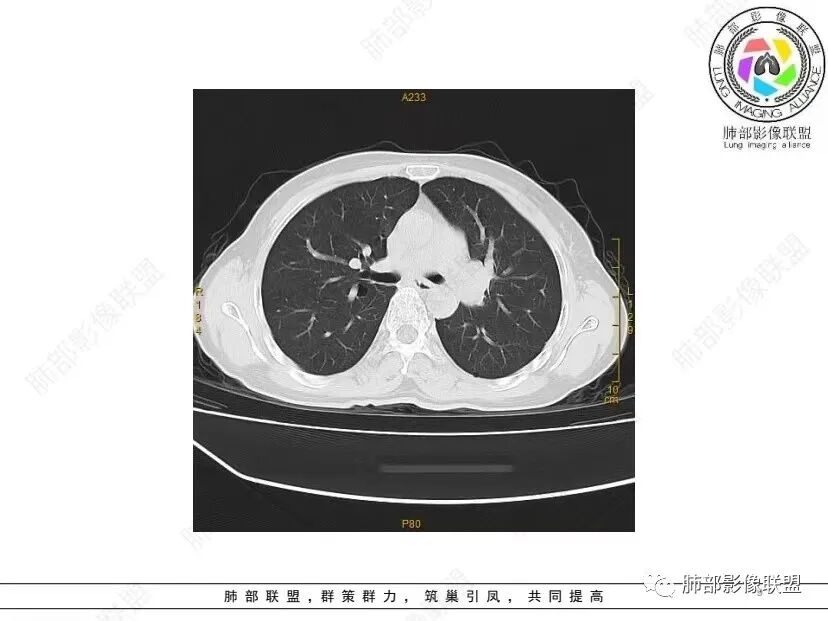

秦化君: 晨读 双肺不均匀散在多发囊状影,大小不等,部分囊形态欠规整,壁薄均匀,部分囊胸膜下平行。双肺少许斑片状磨玻璃影,边缘模糊。考虑BHD综合征。鉴别PCP,LIP。

红日初升: 中年女性,双肺多发气囊,背景干净,大小不一,下肺韧带旁较大,考虑BHD,鉴别LIP、LAM

宇宙: 中年女性,两肺多发大小不等薄壁囊状影,两肺纵膈胸膜下分布明显,考虑BHD,鉴别LAM

这个病例目前影像特点,多囊,囊主要位于下肺,胸膜下及小叶核心为主

伴随少许索条,而且这些病灶与囊不一定有相关性

囊的分布,PLCH基本可以排除

囊壁薄且均匀,光滑,形态规则,基本除外恶性

单纯囊,无斑片及其他实性病灶,感染不支持,可能的是:LAM、BHD、LIP

从囊的分布、大小,BHD可能性可能大一些,但是LIP、LAM都可以这样表现,具体诊断应该是这三种之一,影像缩小到这里我觉得就差不多了,结合临床考虑就行,不支持靠影像强下结论。